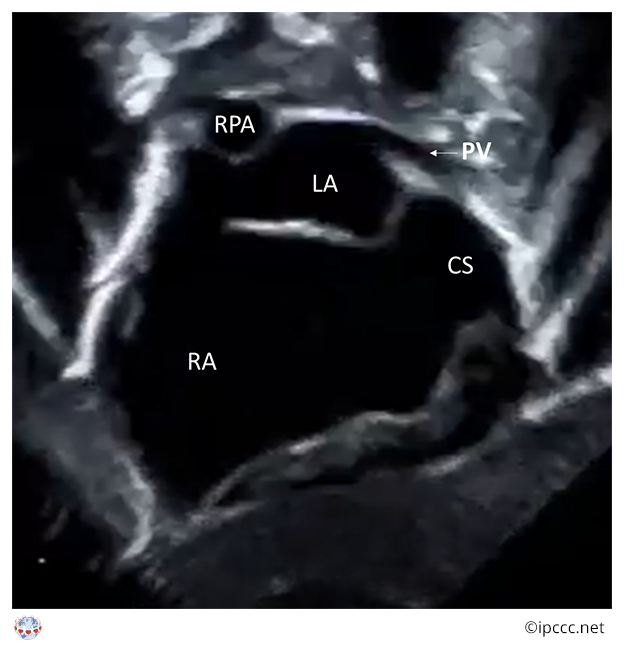

A spectrum of congenital cardiovascular malformations with normally aligned great arteries without a common atrioventricular junction, characterized by underdevelopment of the left heart with significant hypoplasia of the left ventricle including atresia, stenosis, or hypoplasia of the aortic or mitral valve, or both valves, and hypoplasia of the ascending aorta and aortic arch.

Echocardiogram